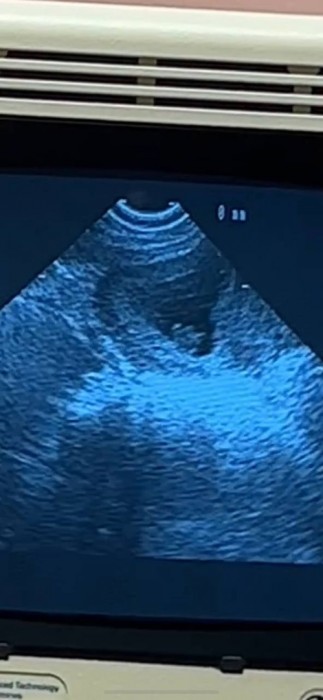

Именно такой ответ пара дала на самый частый вопрос от подписчиков - не скоро. Пока новоиспеченные родители только привыкают к своей ответственной роли и ухаживают за новорожденным. Не обошлось и без проблем - Ане пришлось несколько раз побывать в больнице и даже сделать операцию. Теперь она не может кормить малыша грудью.